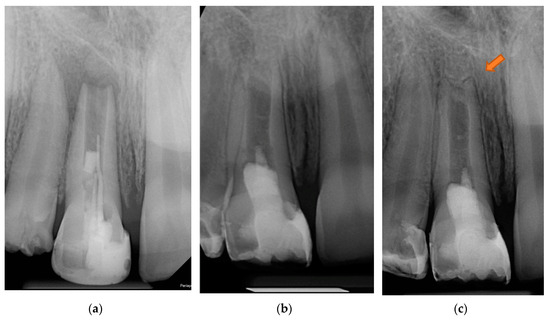

2. Detailed Case Description